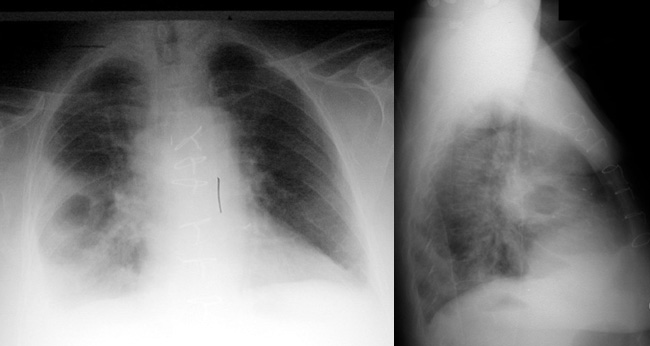

Pseudomonas Pneumonia

Acute rapid progression to cavitation